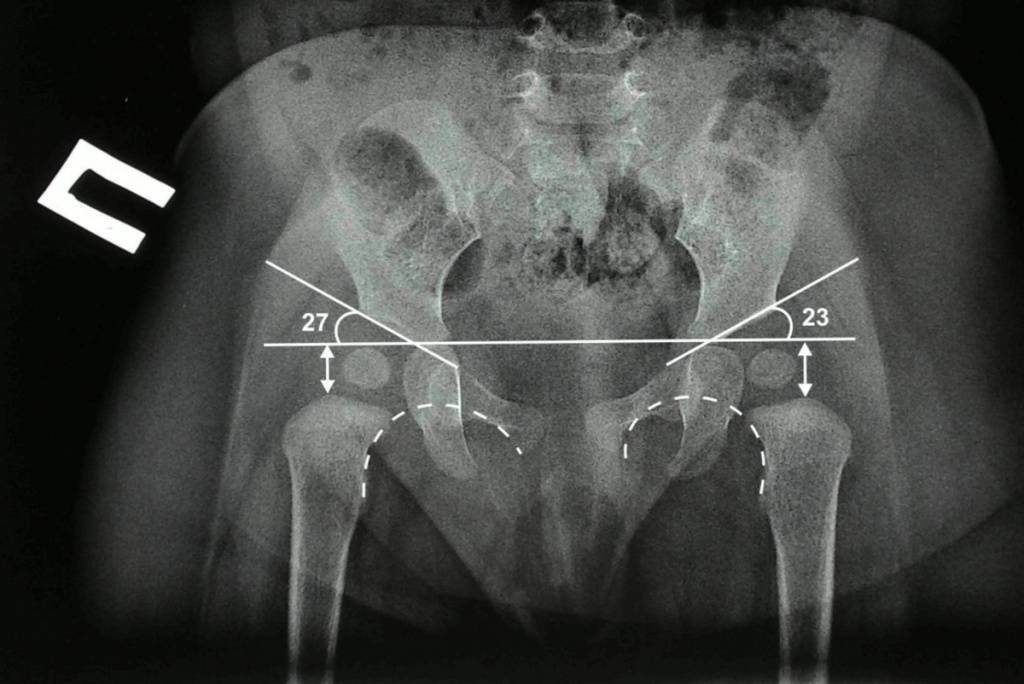

Рентгенологическая диагностика

У новорожденных вертлужная впадина и большая часть бедренной головки представлены хрящевой тканью, поэтому на рентгенологических снимках не видны. Для трактовки результатов используют различные схемы с проведением специальных линий, чтобы рассчитать угол наклона крыши вертлужной впадины. В норме он должен быть не меньше 30° у новорожденных и примерно 20° – у малышей от трех месяцев и старше.

Для расшифровки результатов существует специальная техника, названная схемой Хильгенрейнера. В ней фигурируют такие категории:

- ацетабулярный угол;

- линия Хильгенрейнера;

- расстояние между метафизарными пластинками и линией Хильгенрейнера, обозначаемое буквой h;

- расстояние от h до нижних контуров вестибулярной пластины, обозначаемое как d.

Ацетабулярный угол определяется как область между двумя плоскостями – линией эпсилонобразных хрящей и касательной, проходящей вдоль края суставных впадин.

Линия Хильгенрейнера проводится горизонтально, через У-образные хрящи по нижним точкам подвздошной кости.

Расстояние h отсчитывается от линии Хильгенрейнера до середины метафизарной пластинки проксимального отдела кости бедра. По нему можно отследить, на сколько смещена головка кости бедра по отношению ко впадине сустава.

Промежуток d показывает латеральное смещение головки по сравнению с вертлужной впадиной.

Схема даёт возможность представления сустава в трёхмерной проекции. Даже на самых ранних стадиях она даёт возможность обнаружить большинство патологий и нарушений развития сустава.

Для большей достоверности в схеме предусмотрено проведение дополнительных показателей – линии Кальве и Шентона. Первая из них соединяет верхний край шейки бедра с наружным краем подвздошной кости, и в норме она должна быть непрерывной. Если линия прерывается, это может говорить об отсутствии целостности суставного аппарата.

Линия Шентона представляет собой продолжение окружности вертлужной впадины, в виде проекции на медиальную поверхность шейки бедра. Её разрыв означает латерально-проксимальное смещение бедренной кости.